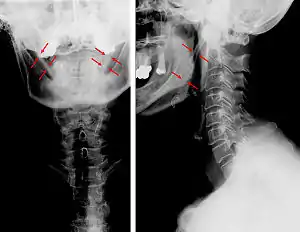

| Anteroposterior and lateral radiographs of cervical spine showing ossification of the stylohyoid ligament on both sides | |

CT scan, coronal section showing bilateral extended styloid process and stylohyoid ligament ossification (incidental finding)

Diagnosis is suspected when a patient presents with the symptoms of the classic form of "Eagle syndrome" e.g. unilateral neck pain, sore throat or tinnitus. Sometimes the tip of the styloid process is palpable in the back of the throat. The diagnosis of the vascular type is more difficult and requires an expert opinion. One should have a high level of suspicion when neurological symptoms occur upon head rotation. Symptoms tend to be worsened on bimanual palpation of the styloid through the tonsillar bed. They may be relieved by infiltration of lidocaine into the tonsillar bed. Because of the proximity of several large vascular structures in this area this procedure should not be considered to be risk free.

Imaging is important and is diagnostic. Visualizing the styloid process on a CT scan with 3D reconstruction is the suggested imaging technique.[11] The enlarged styloid may be visible on an orthopantogram or a lateral soft tissue X ray of the neck.